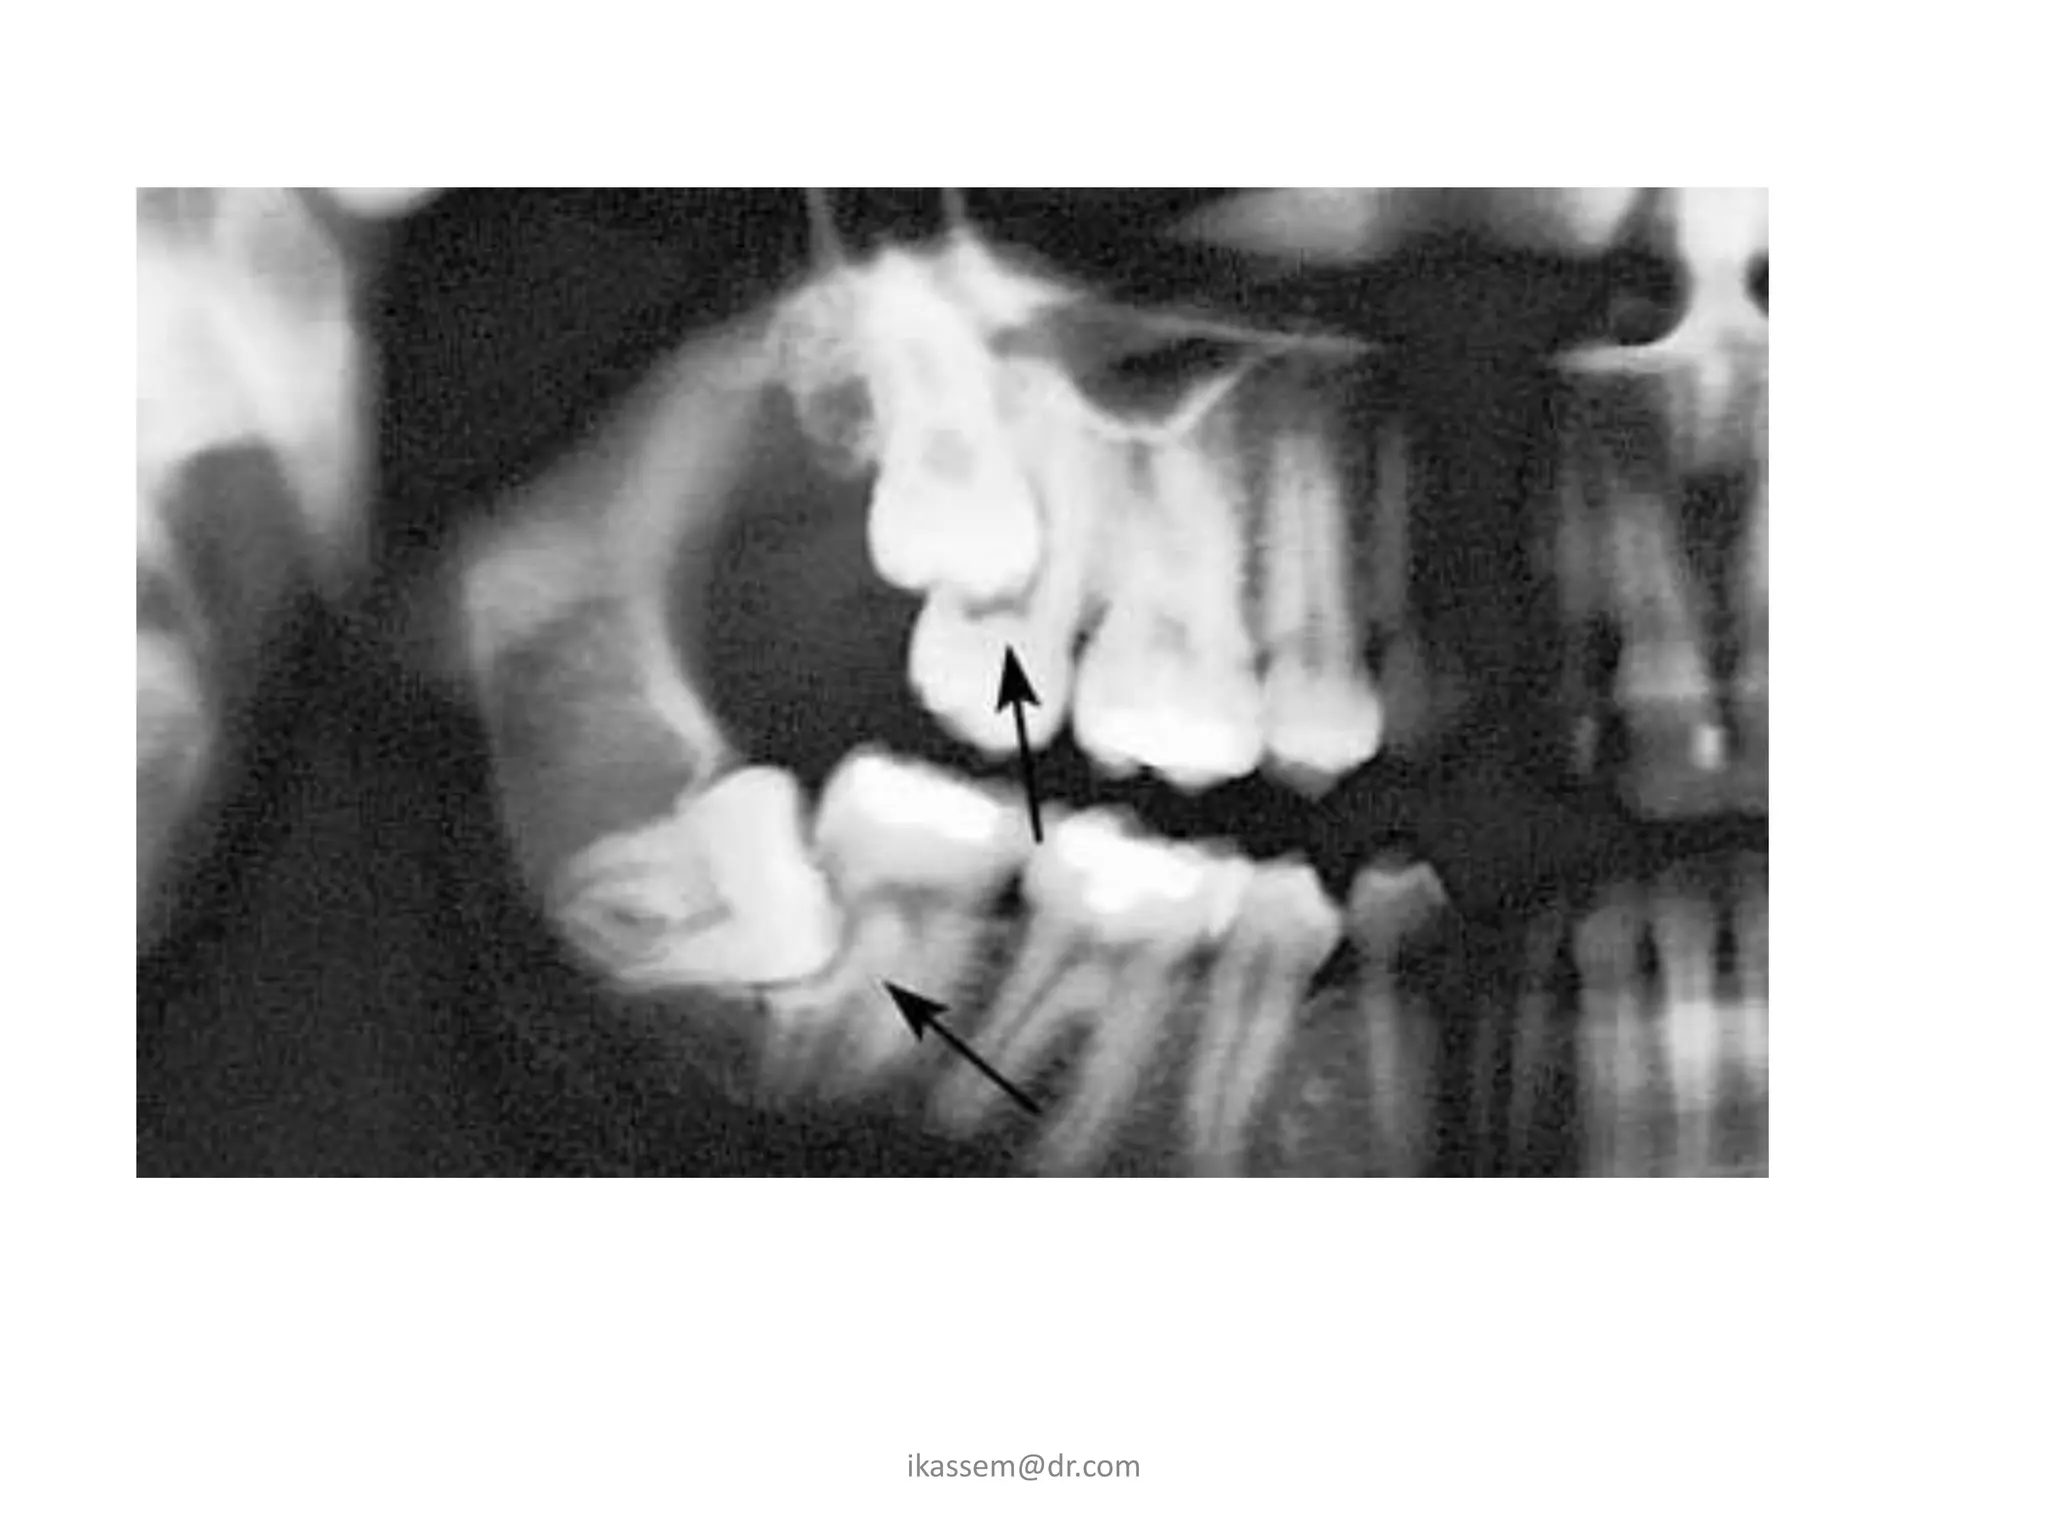

B. Dental Caries

• When third molar is

impacted or partially

impacted ,the bacteria

that cause dental caries

can be exposed to the

distal aspect of the 2nd

molar, as well as to

third molar

C. Periodontal Disease

• Erupted teeth adjacent to

impacted teeth are

predisposed to periodontal

disease.

• As it decrease amount of bone

on the distal aspect of adjacent

2nd molar, with deep

periodontal pocket on the

distal aspect of the 2nd molar.

D. Root Resorption

• Impacted teeth cause

sufficient pressure on

the root of an adjacent

tooth to cause root

resorption.